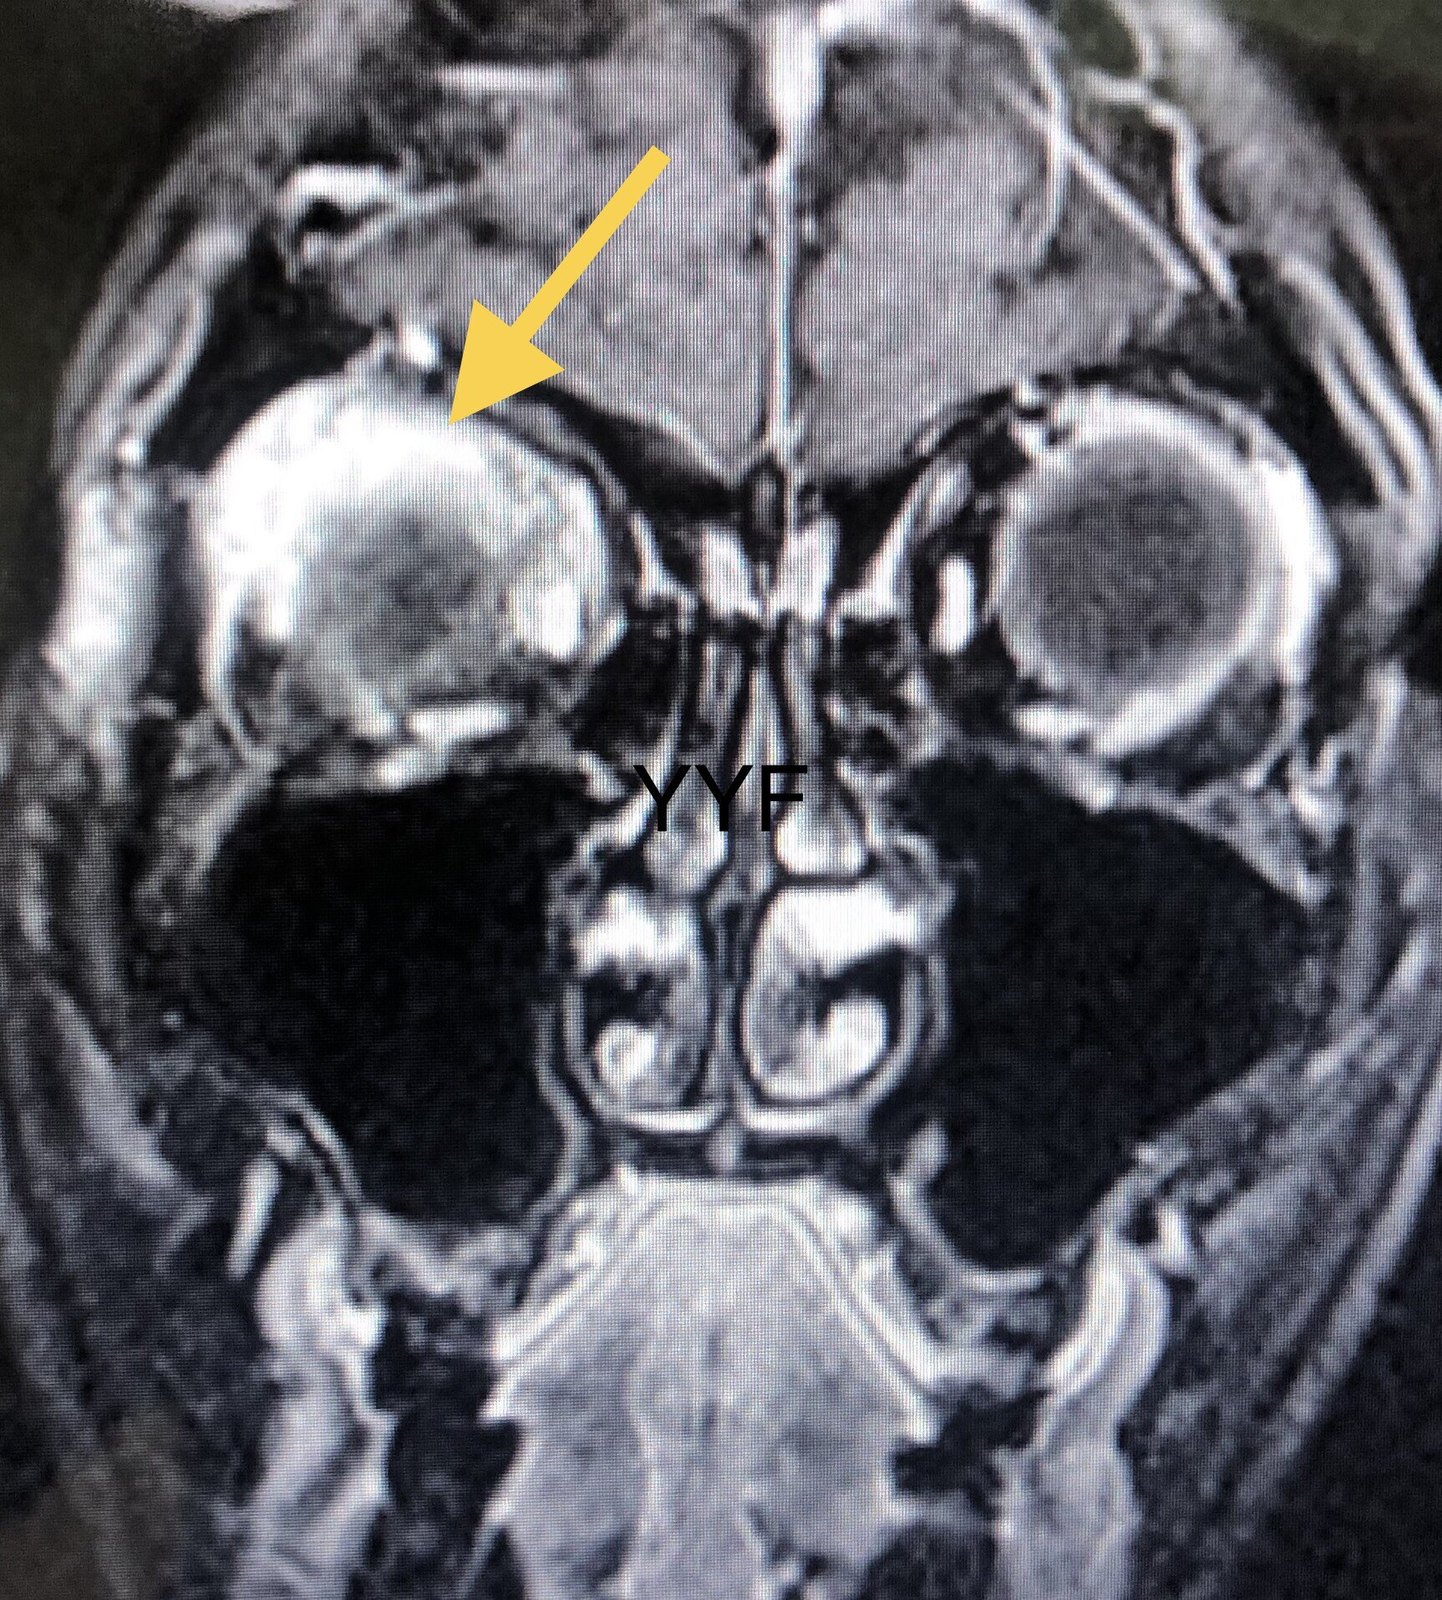

眼眶弥漫性占位

根据临床经验和影像学表现,炎症可能性大。

本例病病变同样累及泪腺区,但远远超出泪腺范围,

最终证明为炎症性病变。

最终的诊断应该是眼眶炎性假瘤弥漫性这一类型。